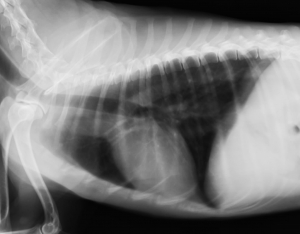

下の写真は悪性皮膚メラノーマの肺転移のレントゲン写真です。(今回のトピックとは違うワンちゃんのものです。)上が肺転移以前の正常なレントゲン画像、下がメラノーマによる転移性肺がんの写真です。本来黒く抜けて見える肺に砲弾状に白く見える転移病巣が多数みられています。